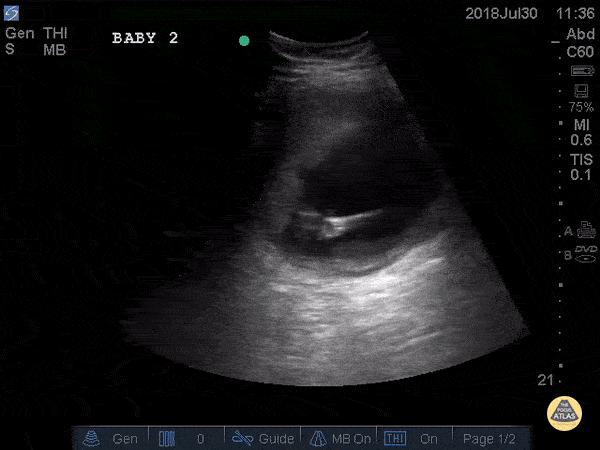

Young female patient at 19 weeks gestation presented s/p syncopal event. POCUS performed and patient had a negative FAST. This image is a transabdominal ultrasound of an intrauterine twin gestation. A placenta can be visualized as the echogenic material superior to the fetuses and the hyperechoic umbilical cord can be visualized in the center of the gestational sac. A normal fetal heart rate (FHR) ranges from 120-170 and is expected as early as 6 week gestational age. This scan shows FHRs of 150 and 158. Fetal movement can also be appreciated on this scan, which is expected at 9-10 weeks gestational age. Dr. Eli Madden, Dr. Julianna Jaramillo - Kings County Emergency Medicine